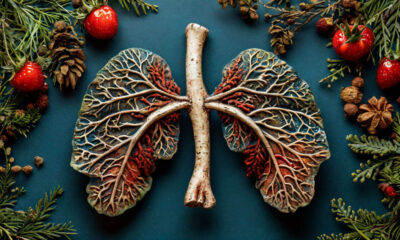

Заболевания20 ноября — Всемирный день борьбы против хронической обструктивной болезни лёгких

Хроническая обструктивная болезнь лёгких (ХОБЛ) — хроническое воспалительное заболевание легких, характеризующееся бронхиальной обструкцией вследствие ремоделирования стенки бронхов,...

ЗависимостьХронические обструктивные заболевания легких (ХОБЛ)

Хронические обструктивные заболевания легких (ХОБЛ) — постоянное нарушение проходимости дыхательных путей, вызванное эмфиземой или хроническим бронхитом.